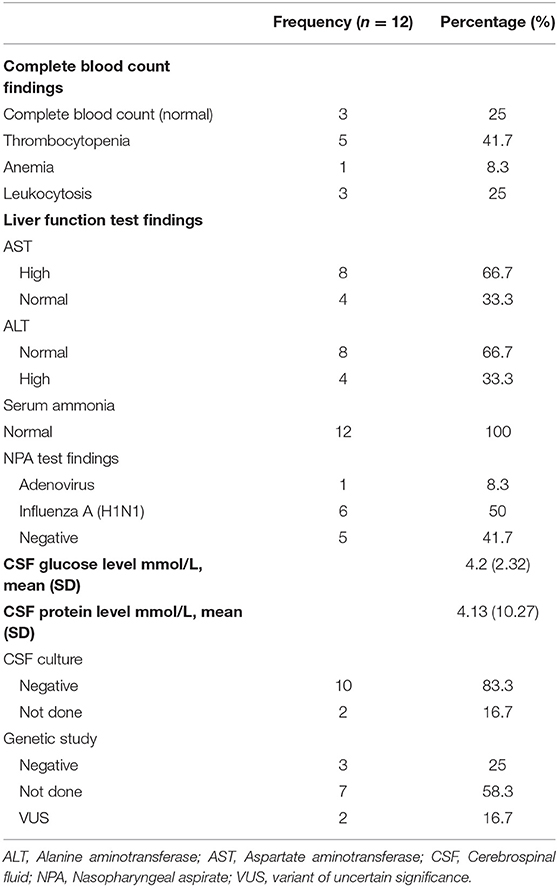

A total of 14 patients with ANEC were identified; two patients were excluded due to the inability to meet the ANEC radiological criteria. Patients' ages ranged from 10 months to 6 years (mean 30.92 months, median 22 months, standard deviation 20.63). Nine patients (75%) were female. All patients presented with preceding febrile illness in the form of upper respiratory tract infection (URTI) symptoms, or gastrointestinal symptoms in the form of vomiting or diarrhea, and altered level of consciousness. Seizures were the initial presentation in eight cases (66.7%). Brain imaging was carried out using Axial, Sagittal, and Coronal T1,T2, FLAIR, diffusion, and susceptibility weighted images which showed characteristic high signal intensity on axial T2 and FLAIR with variable degree of involvement of both thalami in all cases. Diffusion restriction was also seen, while the susceptibility sequence showed dark signal intensity with blooming, indicating hemorrhagic changes. Out of 12 patients, five (41.7%) had brainstem involvement. Follow up brain MRIs were done 2–3 months after the initial presentation, which showed signs of improvement on 33.3%, and 66.7% (n = 8) showed no signs of improvement. The clinical and radiological presentations are summarized in Tables 1, 2. Figures 1–4 show brain MRIs for selected patients.

Figure 2. Brain MRI. Axial T2 (A,B), diffusion (C,D), and susceptibility (E) weighted images. There are swelling and abnormal high signal intensity of pons, bilateral cerebellar white matter (A), both thalami, and bilateral putamen (B) with diffusion restriction (C,D) and dark signal intensity with blooming in the pons (E).